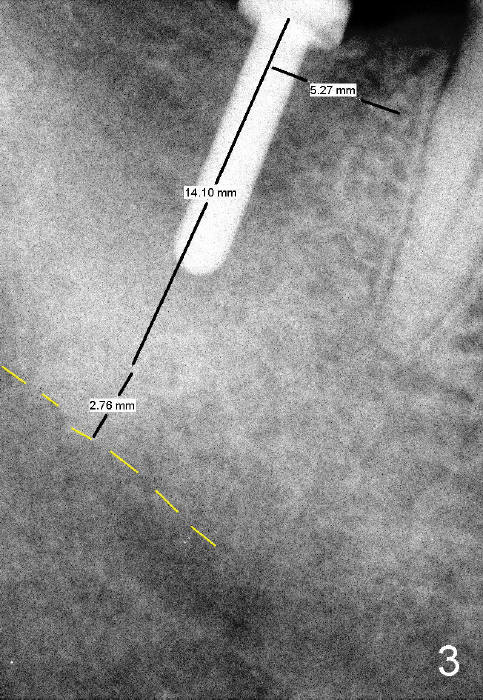

A 53-year-old man requests implant restoration for the lower right 2nd molar (Fig.1: LR2). A 5.3x14 mm submerged tapered implant is planned (Fig.2). PA is taken with a parallel pin after use of a 2 mm drill at the depth of 12 mm (Fig.3). It appears that the length of 14 mm has a safe margin (2-3 mm from the inferior alveolar nerve, yellow dashed line). In addition, the distance from the distal surface of the 1st molar is within normal limit (~5 mm).

With these two parameters under control, it is quick and safe to finish osteotomy with tapered drills with stoppers (Fig.4 <). Stoppers are particularly useful in the posterior region where visibility is limited. The implant is placed as planned (Fig.5, as compared to Fig.2).